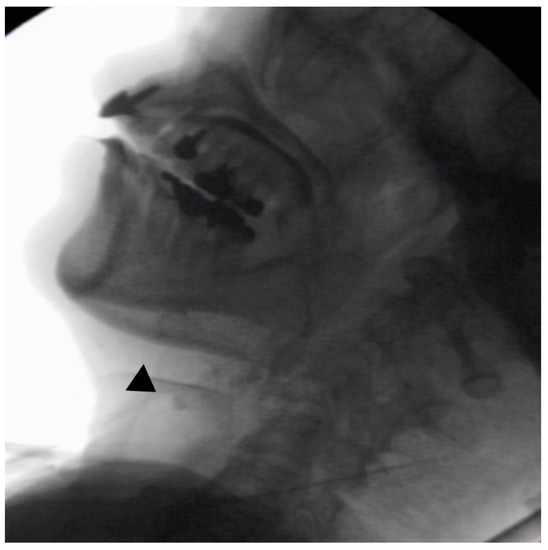

In the seated position, spoon-feeding was infeasible and bolus transport did not occur; furthermore, anterior–posterior tongue movement caused most of the food to dribble out of her mouth. After placing food on top of her tongue using a tube-fitted syringe, most still dribbled out of her mouth (Figure 1a); however, a proportion was transported into the pharynx (Figure 1b). Furthermore, after placing food at the back of her tongue with the patient reclined at 30°, a small amount still dribbled out of her mouth; however, the patient could swallow without aspiration (Figure 2). After increasing the amount placed in her mouth at one time to 7 mL, more food dribbled out of her mouth (Figure 3); additionally, there was a decreased amount transported to the pharynx. When 5 mL of a moderately thick paste was placed in her mouth, none of it dribbled out; however, slight silent aspiration was present (Figure 4). There were no particular issues observed due to peristalsis from the upper esophagus to the stomach.

Figure 1.

(a) Videofluoroscopic examination of swallowing (VF) with the patient sitting up. The test food was 5 mL of an extremely thick paste. Most of the food dribbled out of her mouth, with only a small amount being transported to the pharynx. (b) Maximum hyoid elevation upon deglutition.